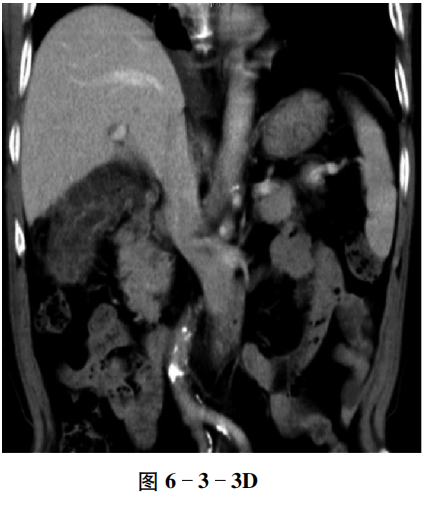

【CT征象】 平扫示胆囊体积明显增大,囊壁不均匀增厚,周围脂肪间隙模糊(图6-3-3A);增强扫描胆囊壁呈多发“串珠状”强化,内见多发线状分隔,呈明显强化,胆囊黏膜线连续,周围肝胆界面模糊(图6-3-3B~D)。

【重要征象】 胆囊壁增厚伴“串珠状”强化。

【病理诊断】 黄色肉芽肿性胆囊炎。

【评述】 黄色肉芽肿性胆囊炎是一种少见的胆囊慢性炎性病变,多数学者认为是由于炎症和阻塞(结石嵌顿、胆汁淤积)共同作用所致,以胆囊壁内形成胆汁性肉芽肿,伴重度增生性纤维化及大量泡沫样细胞为特征。男女均可发病,多数为50~60岁。该病属于良性病变但具有浸润性生长的特点,累及邻近结构时可引起穿孔、脓肿和瘘管形成。

① 胆囊壁弥漫性或局限性增厚,一般厚度超过3 mm。② 胆囊壁内低密度结节,呈串珠样排列时表现为分隔状或栅栏状。③ “三明治”样强化:胆囊壁浆膜层、黏膜层强化,中间肌层不强化,胆囊黏膜线多连续。④ 80%合并胆囊结石和(或)胆管结石。⑤ 浸润性生长,邻近肝实质受累时强化程度低于正常肝实质,胆囊与邻近空腔脏器出现内瘘时,胆囊腔可见积气。